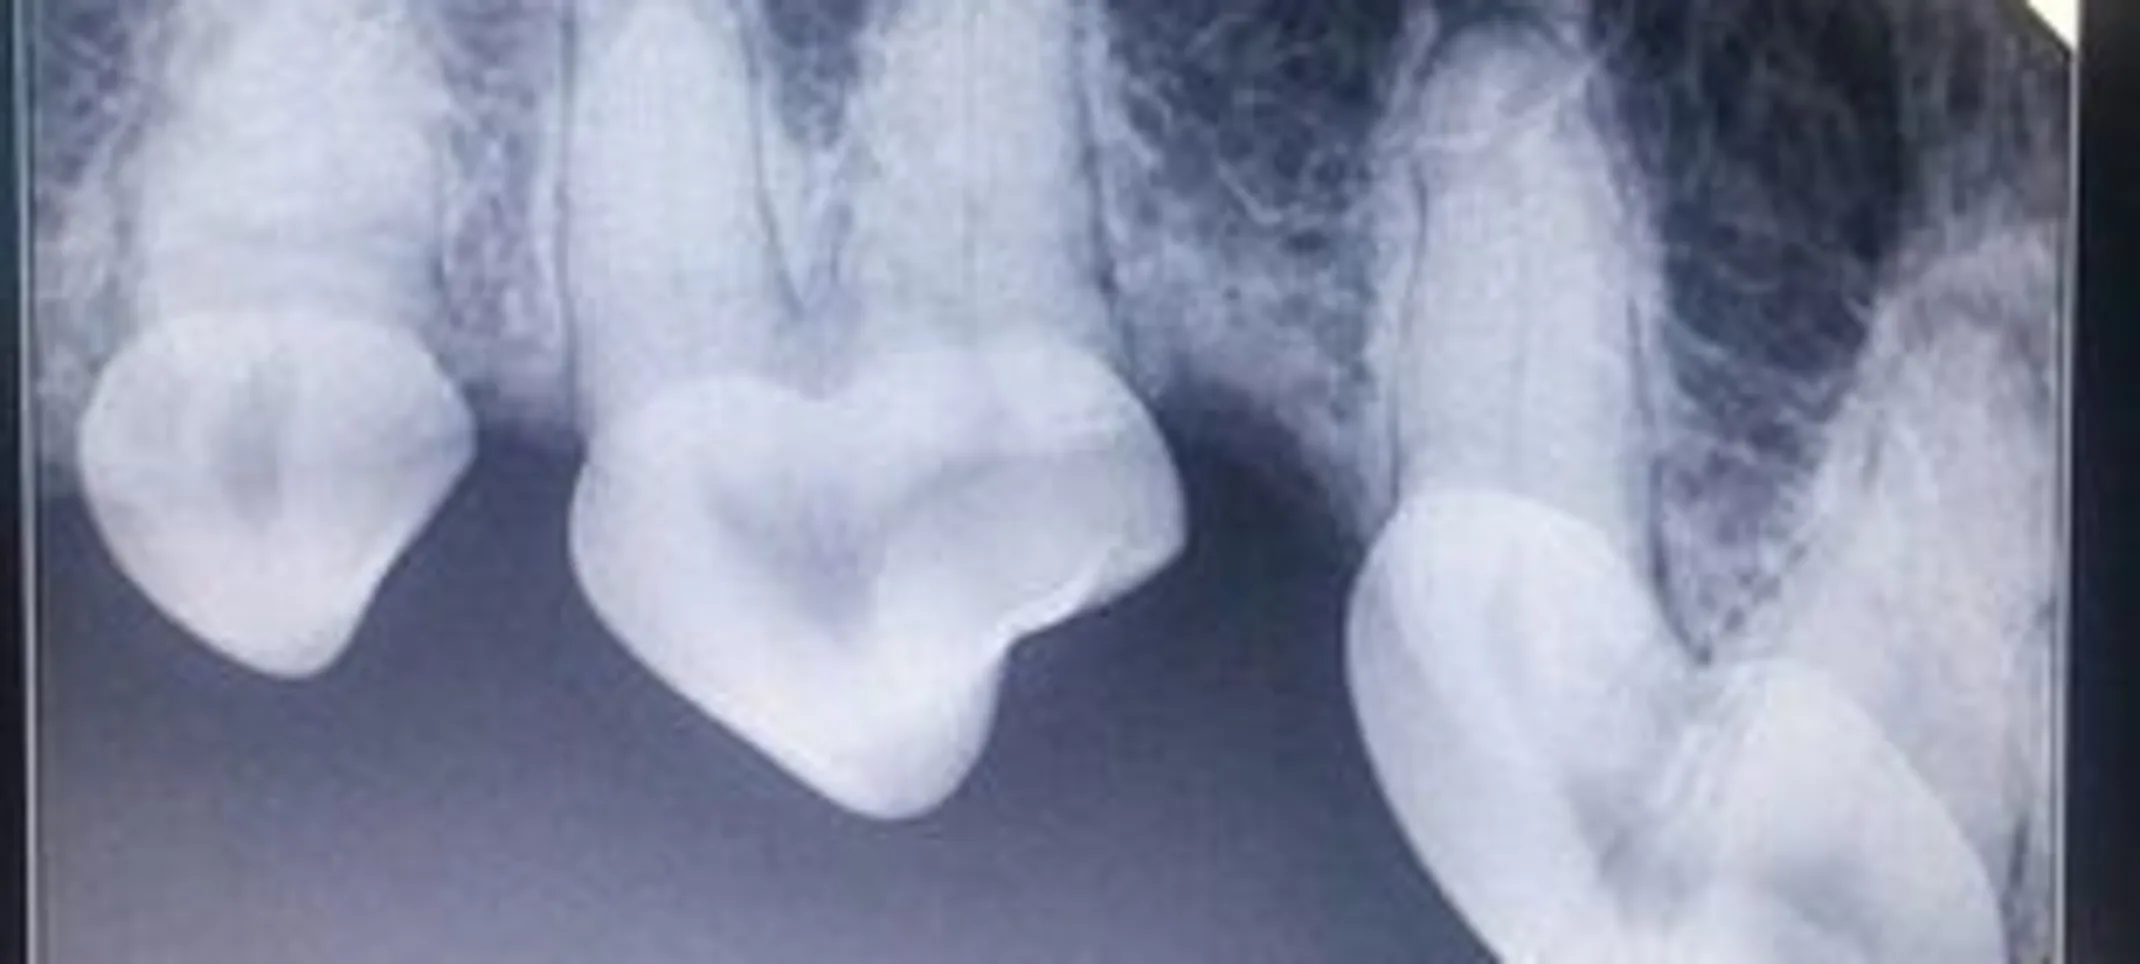

Also similar to human dentistry, we do full mouth radiographs (x-rays) of your pet. This allows our veterinarians to be able to evaluate the roots of your pet's teeth as well as any disease or abnormalities that are located below the gum line and not visible on examination alone.

Dental x-rays give us a unique look at the root health and bone strength below the gum line. Above are some examples of what dental x-rays look like for your pet!